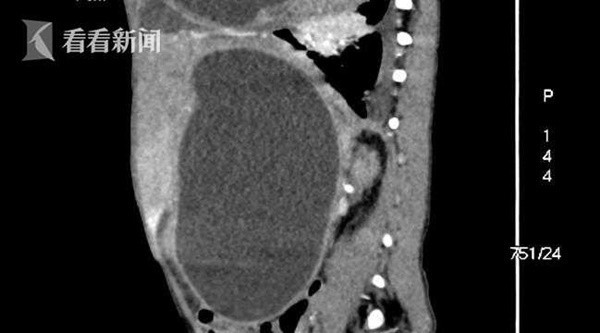

Bác sĩ Vương Kiến Nghiêu, khoa ngoại, bệnh viện Shenzhen Children"s Hospital, cho biết: "Kết quả chụp CT cho thấy vùng bụng và ngực của bệnh nhi có 2 u nang lớn. Đặc biệt u nang vùng ngực có kích thước rất lớn đã chèn ép phổi bên phải.

Kết quả xét nghiệm máu cho thấy, bệnh nhi mắc bệnh sán chó hay còn gọi là sán kim. Nang sán chứa hàng triệu đầu sán. Nếu nang sán vỡ, sẽ phóng thích hàng triệu đầu sán non theo máu ký sinh khắp nơi trên cơ thể như phổi, gan, lách, não, gây ra sự nhiễm độc, khiến việc phẫu thuật trở nên khó khăn".